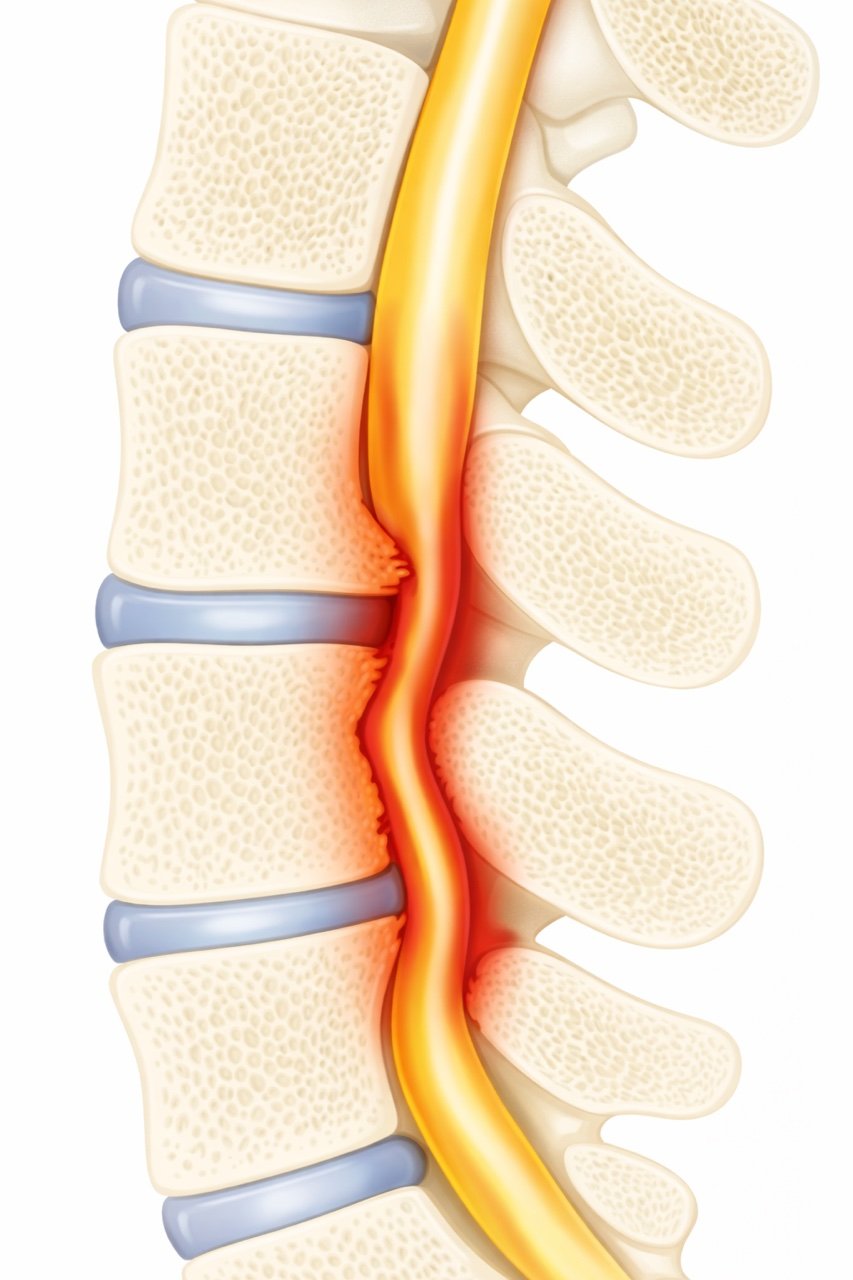

An illustration of a human spine showing a herniated disc pressing on a spinal nerve with inflammation.

Lumbar spinal stenosis means that the space around the nerves in the lower back has become too narrow.

The spinal canal normally protects the nerves that travel from the spine into the legs. When this space narrows, the nerves can become compressed, leading to pain, numbness, or weakness in the legs.

These changes gradually reduce the space available for the nerves.